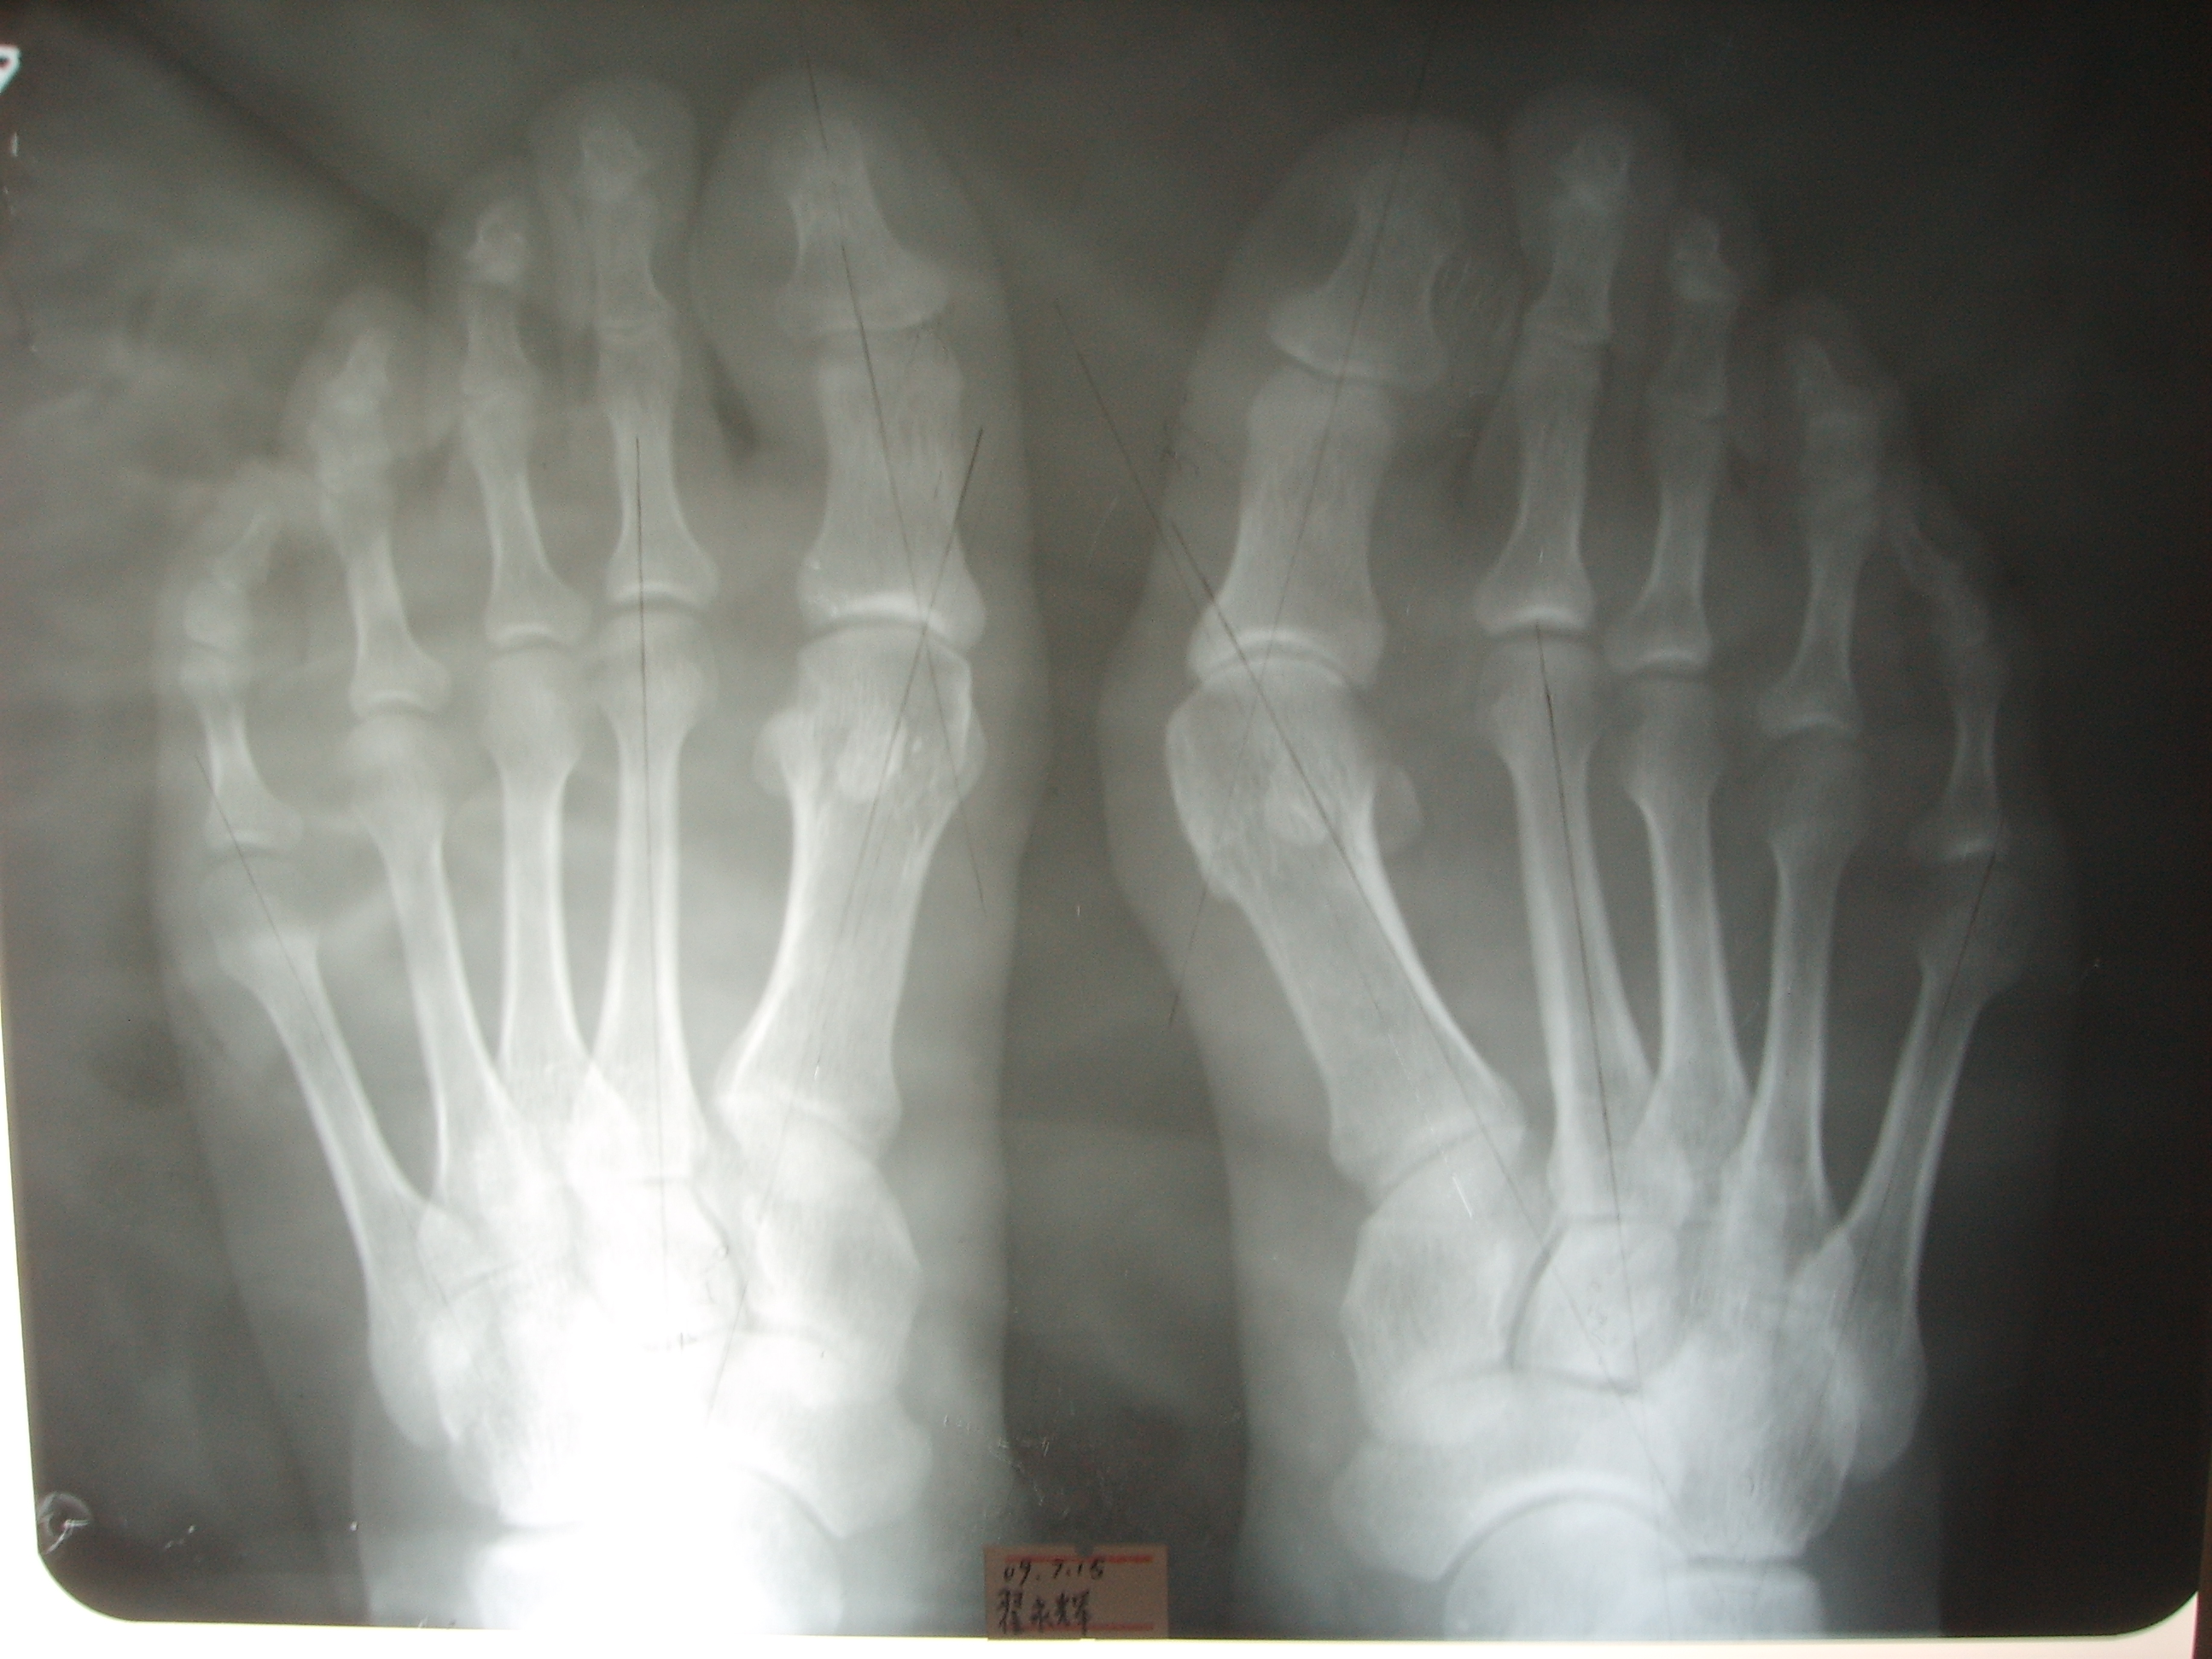

大脚骨X光

从他的脚X光片可以清楚看到,大拇趾稍微有点向外侧偏斜,第一跖骨向内侧偏斜,小拇趾也有凸起,关节对合情况其实还算比较好,不算特别严重的拇外翻,一般来说,男性拇外翻多更轻微,我先前告诉他:其实他这样情况不做手术也没有关系,但是他一再要求手术,因为局部疼痛明显。